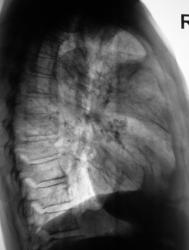

деформация правого корня. Он смещён немного вверх. Картина похоже на течение онкопроцесса.

Новообразование в области правого верхнедолевого бронха, центральная форма, ателектаз или обструктивный пневмонит в третьем сегменте, лимфангит во всей доле, расширение вехнего средостения вправо - метастазы?

Валентин Львович, а Вы не хотите сделать боковую томограмму через тень (корень) и томограмму на правый в/долевой бронх. Потому как ни одной из томограмм ни тень, ни бронхи справа не в срезе, а есть у меня такое впечатление, что имеет место периферический узел в S3, проекционно накладывающийся на тень корня, кроме того, при таком конгломерате в корне, должна быть более выражена гиповентиляция...